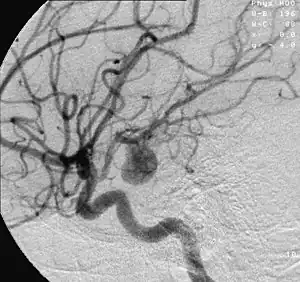

| 腦動脈中動脈瘤的血管造影,動脈瘤是中間灰色的豆狀物體 | |